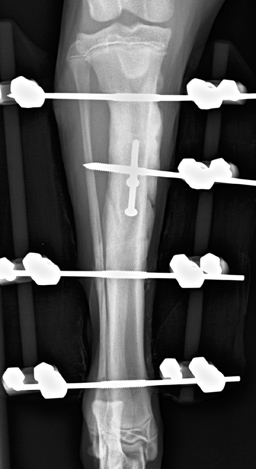

Mein Forschungsinteresse liegt in der Orthopädie. Bereits während meines chirurgischen Spezialistentrainings an der Universität Lüttich habe ich begonnen, mich mit den komplexen Anforderungen der Knochenheilung auseinander zu setzen. Die optimale Frakturheilung hängt von verschiedenen Faktoren ab, wie z.B. Weichteiltrauma, Art und Lokalisierung der Fraktur, Alter des Tieres etc. Dadurch ist jeder Knochenbruch sehr individuell und eine standardisierte Frakturversorgung ist nicht möglich oder ratsam. Stets gilt es, eine Balance zwischen ausreichender Stabilität und erforderlicher Elastizität zu schaffen und gleichzeitig die Anzahl und Art der Implantate anzupassen. |

Wie Frakturen entstehen, wie die Stressverteilung im Knochen vor Auftreten der Fraktur und nach Osteosynthese verläuft, und welche Implantate bei den jeweiligen Frakturtypen verwendet werden sollten, ist derzeit unser Forschungsschwerpunkt. Die Auswahl der Implantate basiert derzeit oft auf Erfahrungswerten und mechanischen Tests, ist aber in vielen Fällen klinisch noch nicht wissenschaftlich validiert. Mit unserem Forschungsprojekt soll diese Validierung anhand von Computersimulationen ermöglicht werden. Zu diesem Zweck werden verschiedenen Frakturtypen und Frakturlokalisationen an einem Computermodell nachgebildet und die klassischen Implantate simuliert. Bereiche verstärkter Beanspruchung werden sichtbar gemacht und Verbesserungsvorschläge können am Computer getestet werden. Langfristig soll eine Computersoftware erarbeitet werden, die den Kleintierchirurgen eine Entscheidungshilfe an die Hand gibt.